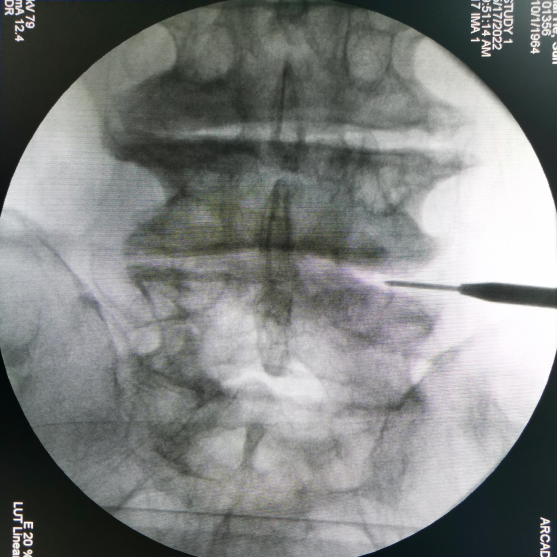

腰椎側(cè)前方椎間融合術(shù)——OLIF技術(shù)(Oblique Lumber Interbody Fusion)是目前最新的一種腰椎融合入路技術(shù)。

該術(shù)式具有創(chuàng)傷小、手術(shù)時間短、術(shù)中出血少、融合率高、住院時間短及快速康復(fù)等優(yōu)勢,且基本不需要神經(jīng)電生理監(jiān)測設(shè)備。因此,無論從臨床效果還是從衛(wèi)生經(jīng)濟學(xué)考慮都具有相當?shù)膬?yōu)勢。

安全簡單的操作方式

限深可調(diào),融合器植入位置更精準